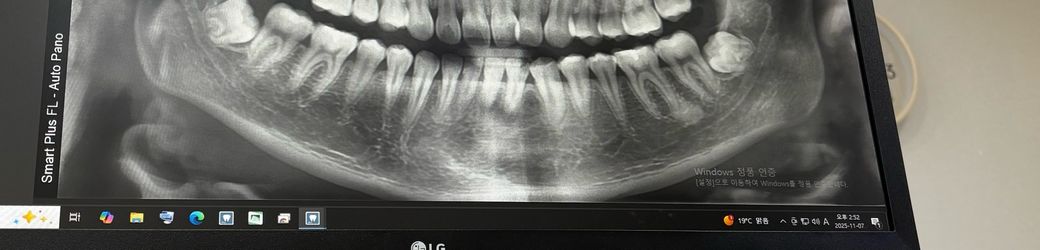

답변부탁드려요ㅠ매복사랑니 발치 난이도 확인해주세요

사진 기준 왼쪽 오늘 뽑고 왔는데요

근데 제가 보기엔 왼쪽 신경선이 사랑니에 눌린 것 처럼 보이는데 맞나요 ㅠ? 오른쪽 다음 주에 뽑는데 왼쪽보다 덜 할까요? 오른쪽은 그래도 신경보다 살짝 위에 있눈 엇 같은데…

발치 자체는 크게 어렵진 않지만, 아직은 사랑니가 다 성장이 안끝난거 같아서 잇몸절개를 해서 발치를 하셔야될것같습니다.

왼쪽사랑니 보다는 반대편 사랑니가 난이도는 더 쉬워보입니다만 엑스레이 사진상으로는 한계가 있습니다.